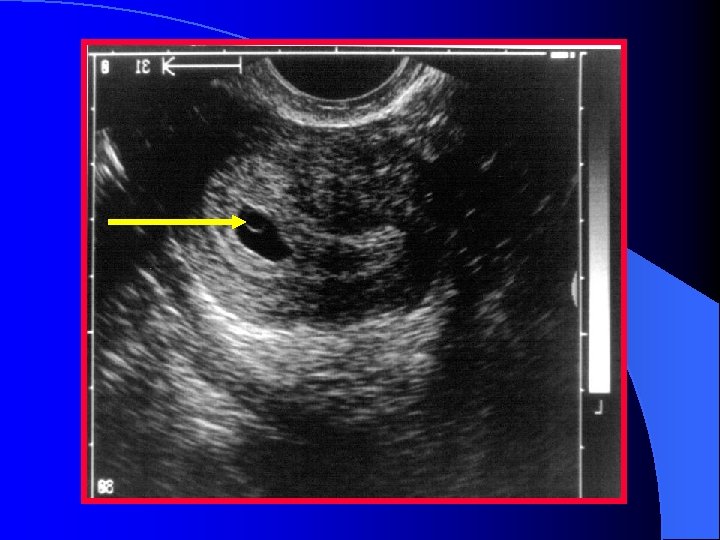

Extrauterine Gestational Sac Extra-uterine mass containing a thick, brightly echogenic ring surrounding an anechoic area l Brightly echogenic appearance may be helpful l Tubal ring l

Adenexal Mass